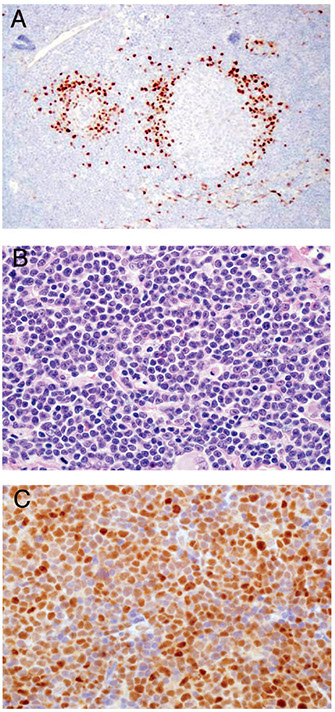

Thioflavin S (fluorescent scope needed)

IHC for Ig light chains, P component (found in most forms of amyloid), Amyloid A

Has become more and more routine to analyze amyloid with mass spec

- becoming the gold standard for amyloid typing

- IHC classification has well-known errors